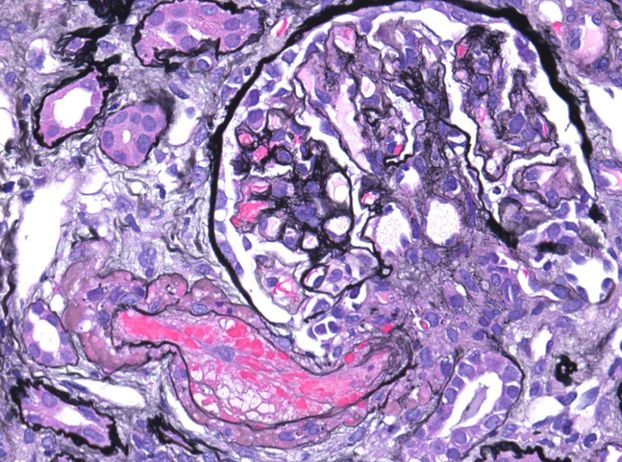

A startling biopsy. Severe acute TMA in a pt with suspected scleroderma renal crisis. Massive vascular thrombosis, mucoid intimal edema, and early onion skin change associated with severe cortical necrosis. #renalpath #nephsky #pathsky